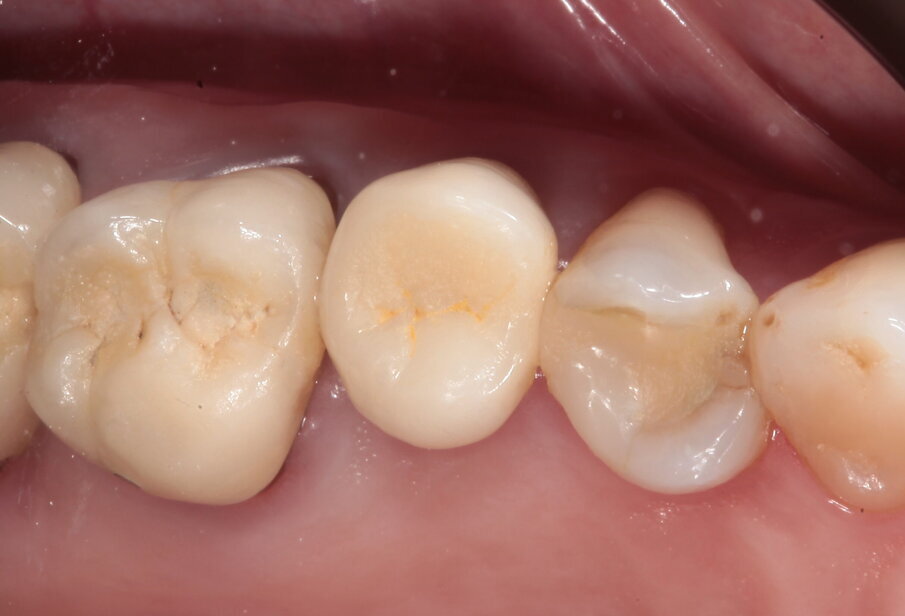

La paziente si presenta in visita lamentando mobilità e l’insorgenza di un dolore alla masticazione a carico dell’elemento 25. Clinicamente l’elemento presenta una corona in ceramica integrale realizzata anni prima (non ricorda quanti) presso altra sede, mobilità di II grado e sondaggio di 9 mm sul versante palatale.

Si presenta inoltre dolente alla percussione. Si riscontra anche l’assenza di risposta al test di vitalità dell’elemento 24, sul quale la paziente riferisce sia stata effettuata una medicazione endodontica da un collega come tentativo di risolvere la sintomatologia dolorosa a carico dell’elemento 25 (Figg. 1-3).